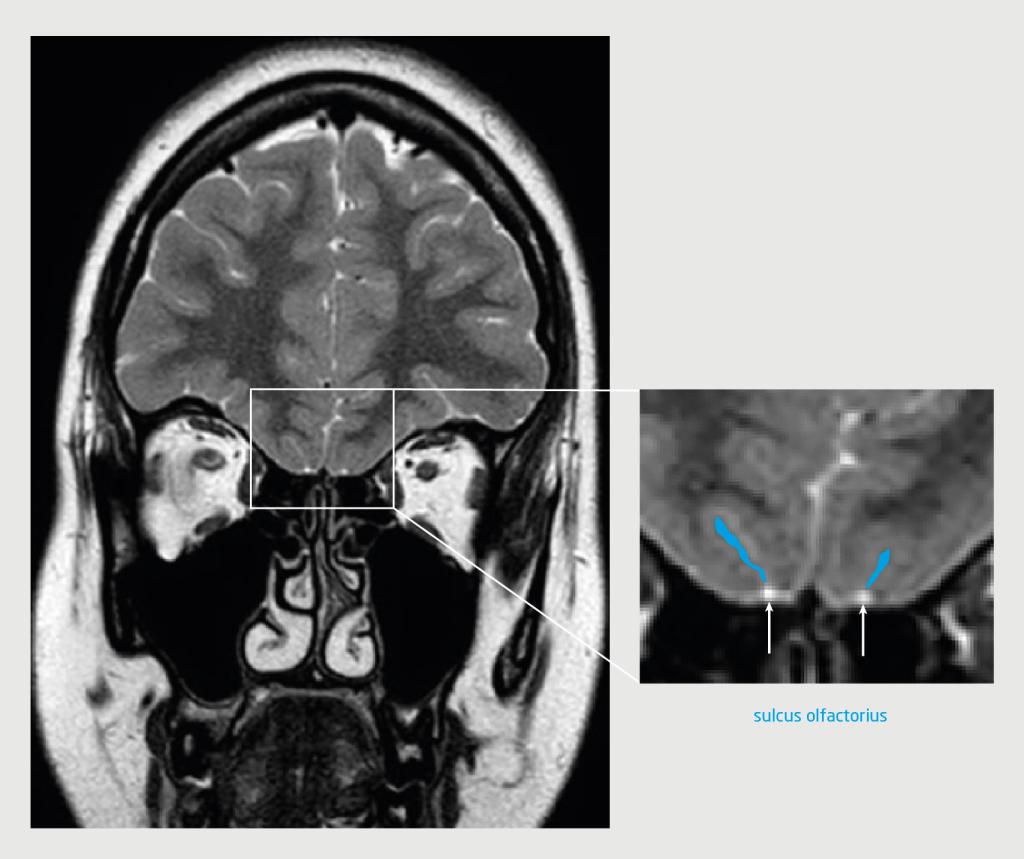

Patiënt C, een 53-jarige vrouw met idiopathische intracraniële hypertensie, bezocht de polikliniek KNO vanwege een afwezigheid van reukvermogen. Dit had zich langzaam progressief ontwikkeld. Zij had geen rinosinogene klachten en het KNO-onderzoek liet een vrije reukspleet en rustig slijmvlies zien. De score op de reuktest paste bij anosmie. Een MRI-scan liet beiderzijds een verwijd cavum van Meckel zien, een partieel ‘empty sella sign’ en een prominente hoeveelheid liquor bilateraal rondom de n. opticus en n. oculomotorius ter hoogte van de sinus cavernosus, passend bij intracraniële hypertensie. De n. olfactorius had beiderzijds een hypoplastisch aspect, waarschijnlijk door compressie bij chronisch verhoogde druk (figuur 2).

Figuur 2 | De hersenen van de patiënte met intracraniële hypertensie

T2-gewogen turbospinecho-MRI van de hersenen van patiënt C (coronale coupe). Op deze scan van de voorste schedelbasis ter hoogte van de fossa olfactorius is bilateraal een hypoplastische, concave bulbus olfactorius te zien.